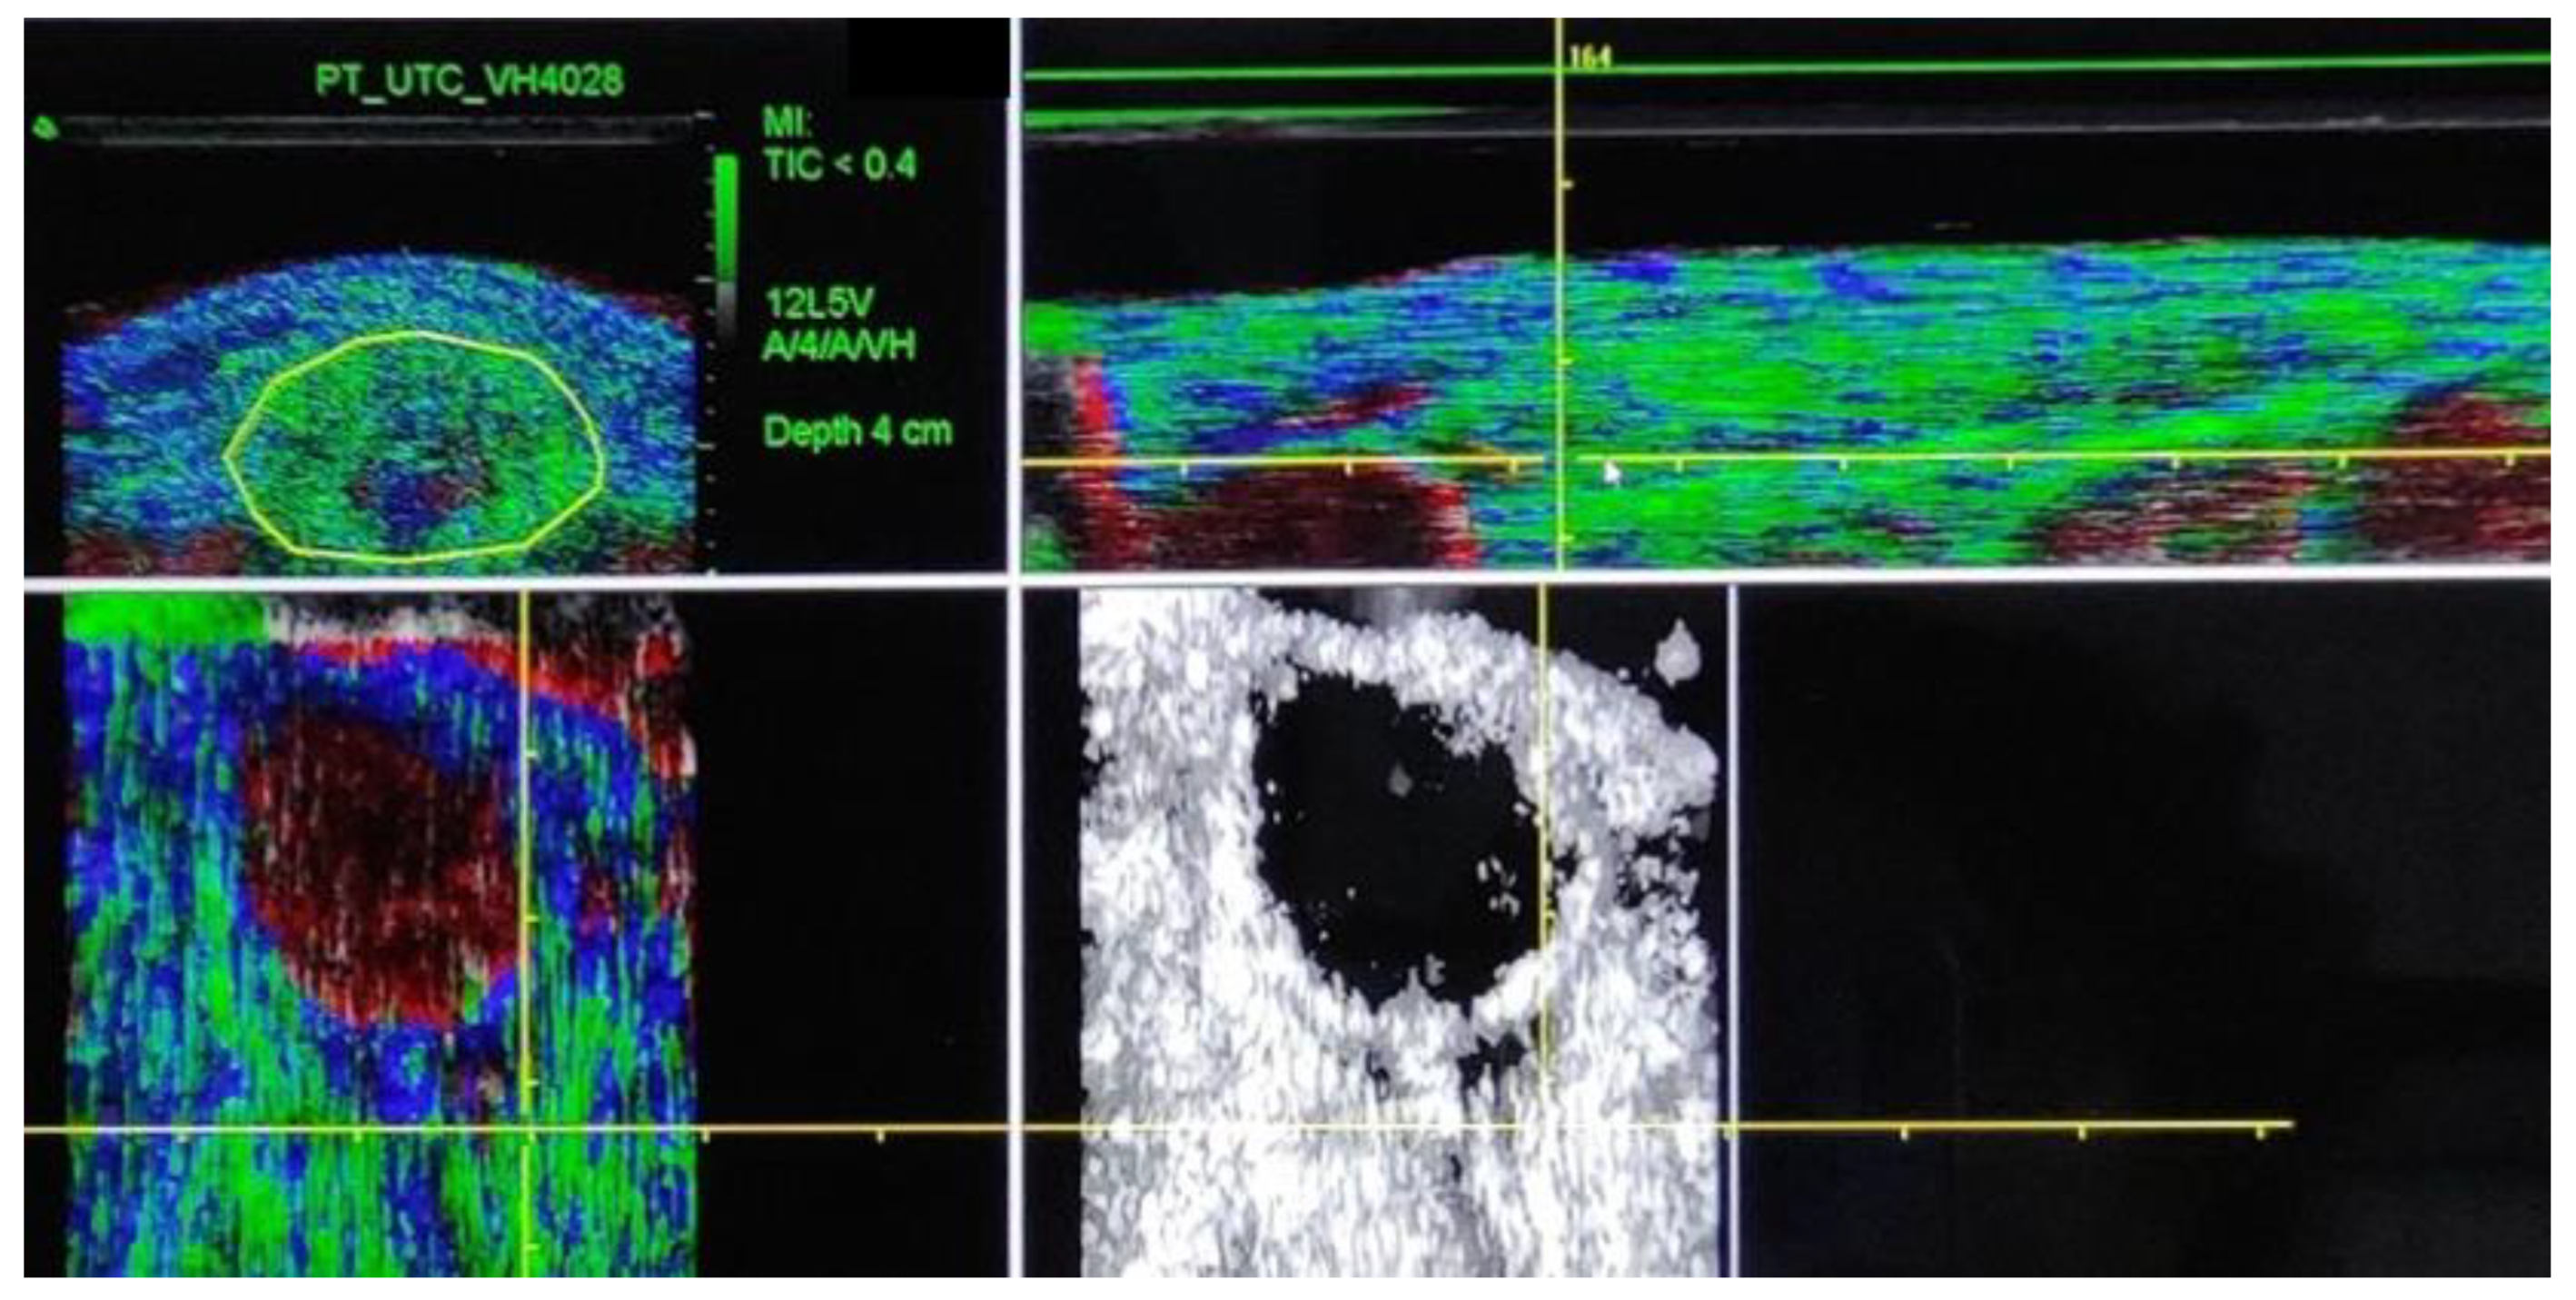

2. Materials and Methods

2.2. Procedure